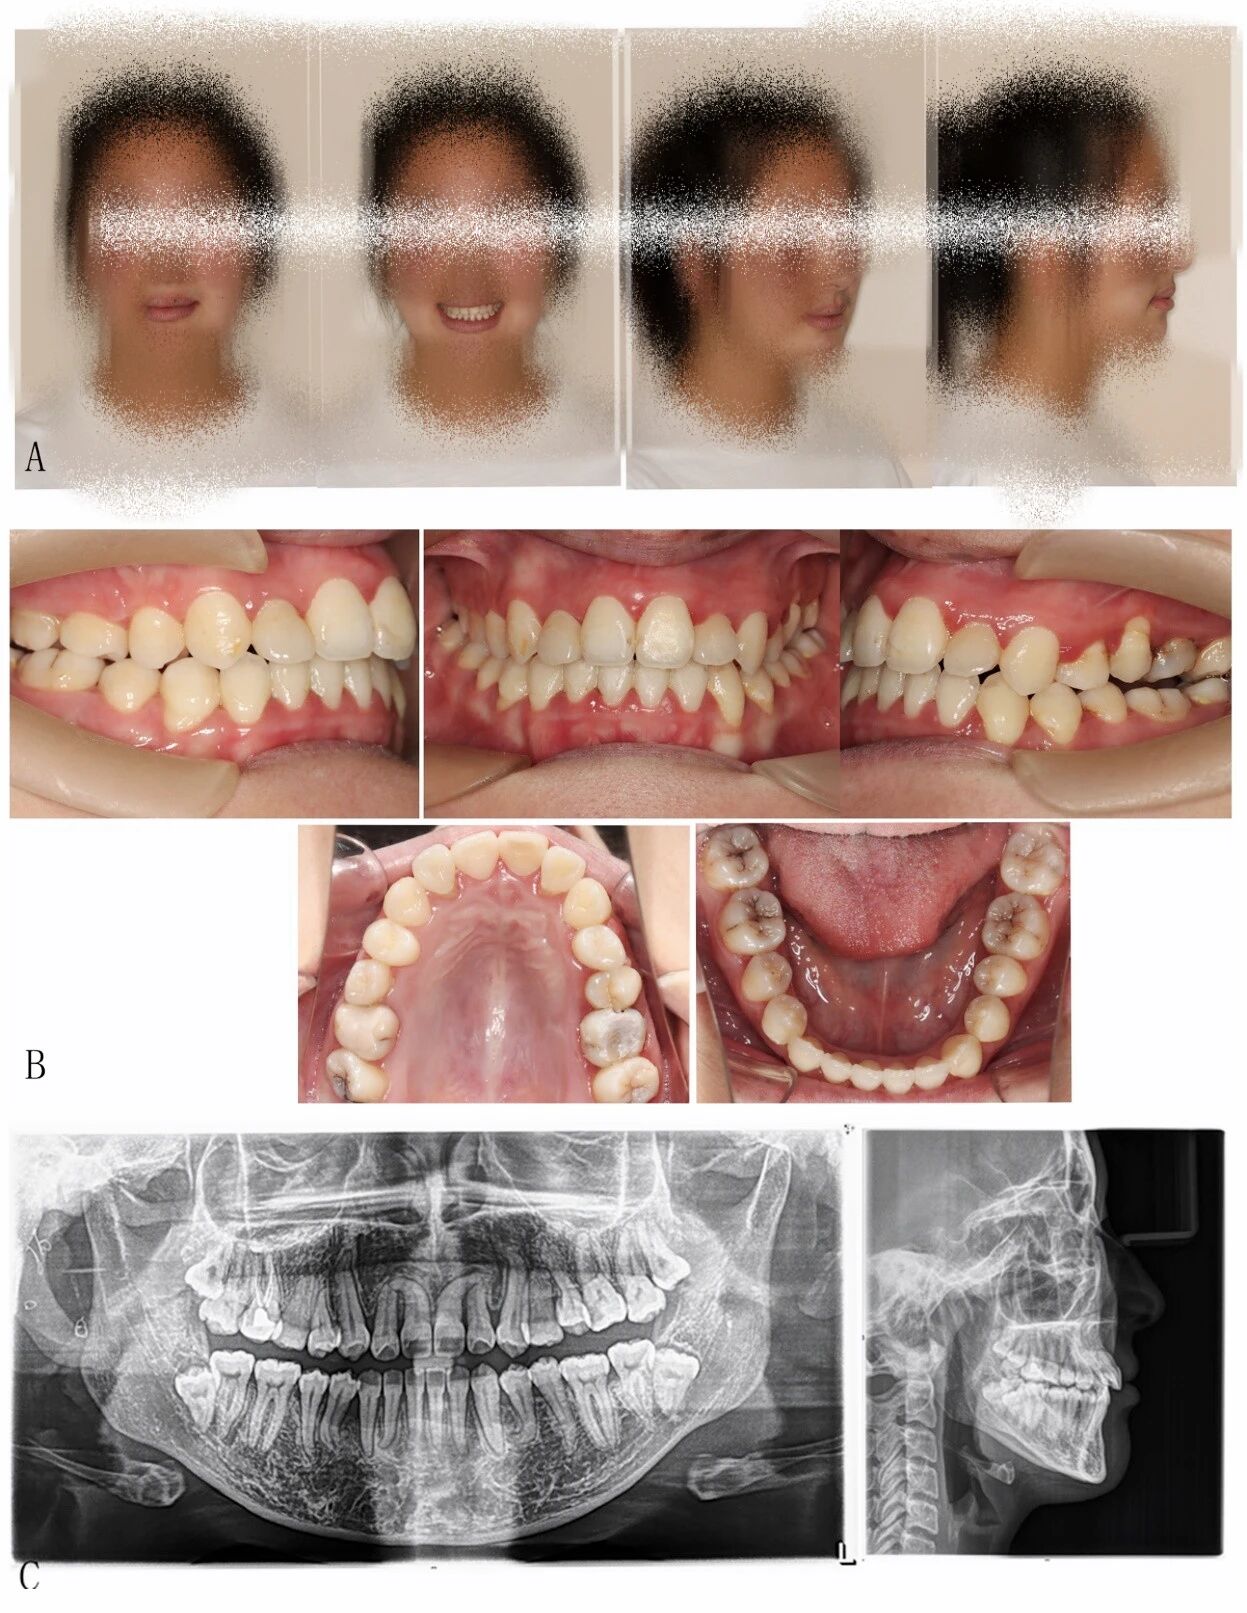

图1:治疗前面相(A)、口内相(B)、曲面断层片、头颅侧位片及胸片(箭头处为怀疑锁骨缺如处)(C)

这就造成了,曲面断层片上,牙齿纵横交错,情况非常复杂!

同时,X光片还提示伴有锁骨部分缺如、面部不对称等,这些全身特征高度指向一种罕见的遗传性疾病:颅骨锁骨发育不全综合征(CCD)。